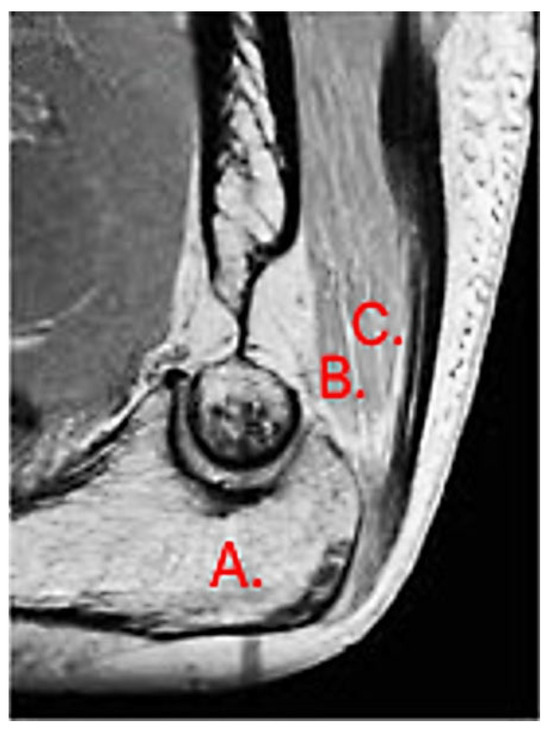

The most common tendon injuries are rotator cuff tears of the shoulder, hand flexor injuries, and achilles tendon injuries [1]. Triceps tendon rupture is the least reported among all the tendon injuries in the literature [2,3]. 65 years ago, Anzel evaluated a series of 1014 patients with tendon ruptures in various locations, and triceps tendon ruptures accounted for only 0.8% of this series [4]. Currently the prevalence is increasing, and the prevalence of triceps tendon injuries has been found to be 3.8% [5]. Theoretically, the types of tendon injuries are tendon avulsion or inside the muscle belly. In practice, a rupture almost always occurs in the area of the tendon-bone junction, and the cause is an eccentric contraction of the triceps causing a tendon deformity of more than 8% [6]. Traditionally the triceps tendon has a uniform attachment to the olecranon ulnae. This premise has caused problems in assessing the degree of damage in traumatic triceps tendon ruptures. In 2006, an anatomic study by Madsen confirmed that in most cases the medial head of the triceps has a single attachment to the olecranon ulnae [7]. This insertion is located in a deeper layer and forms a narrower part of the attachment, and very rarely is only this part damaged [8]. The long and lateral head of the triceps has a common attachment that runs more superficially, gradually extending laterally into the surrounding area towards the musculus anconeus, which helps to strengthen the bone-tendon junction. The width of the attachment correlates with the size of the olecranon and ranges from 20 to 40 mm. Paradoxically, the thickness of the tendon is not as pronounced. The attachment itself occupies a large surface area, reaching 400 mm2 in diameter and is dome-shaped [9]. These current findings are particularly important in partial tendon ruptures when a decision has to be made whether to proceed conservatively or with surgical revision. MRI is an appropriate method of choice to accurately assess the current condition. A schematic representation of the three basic types of partial DTTR rupture can be seen in Figure 1, while the normal anatomic attachment relationships of the triceps tendon in sagittal section to the olecranon ulna and a sub-complete rupture of the triceps tendon of the right hand are shown in Figure 2 and Figure 3. Furthermore, the place of attachment of the individual heads of the triceps to the olecranon ulnae is presented in Figure 4.

Figure 3. Sub complete rupture of the triceps tendon of the right hand (own source). Yellow line: that is the place of the rupture.